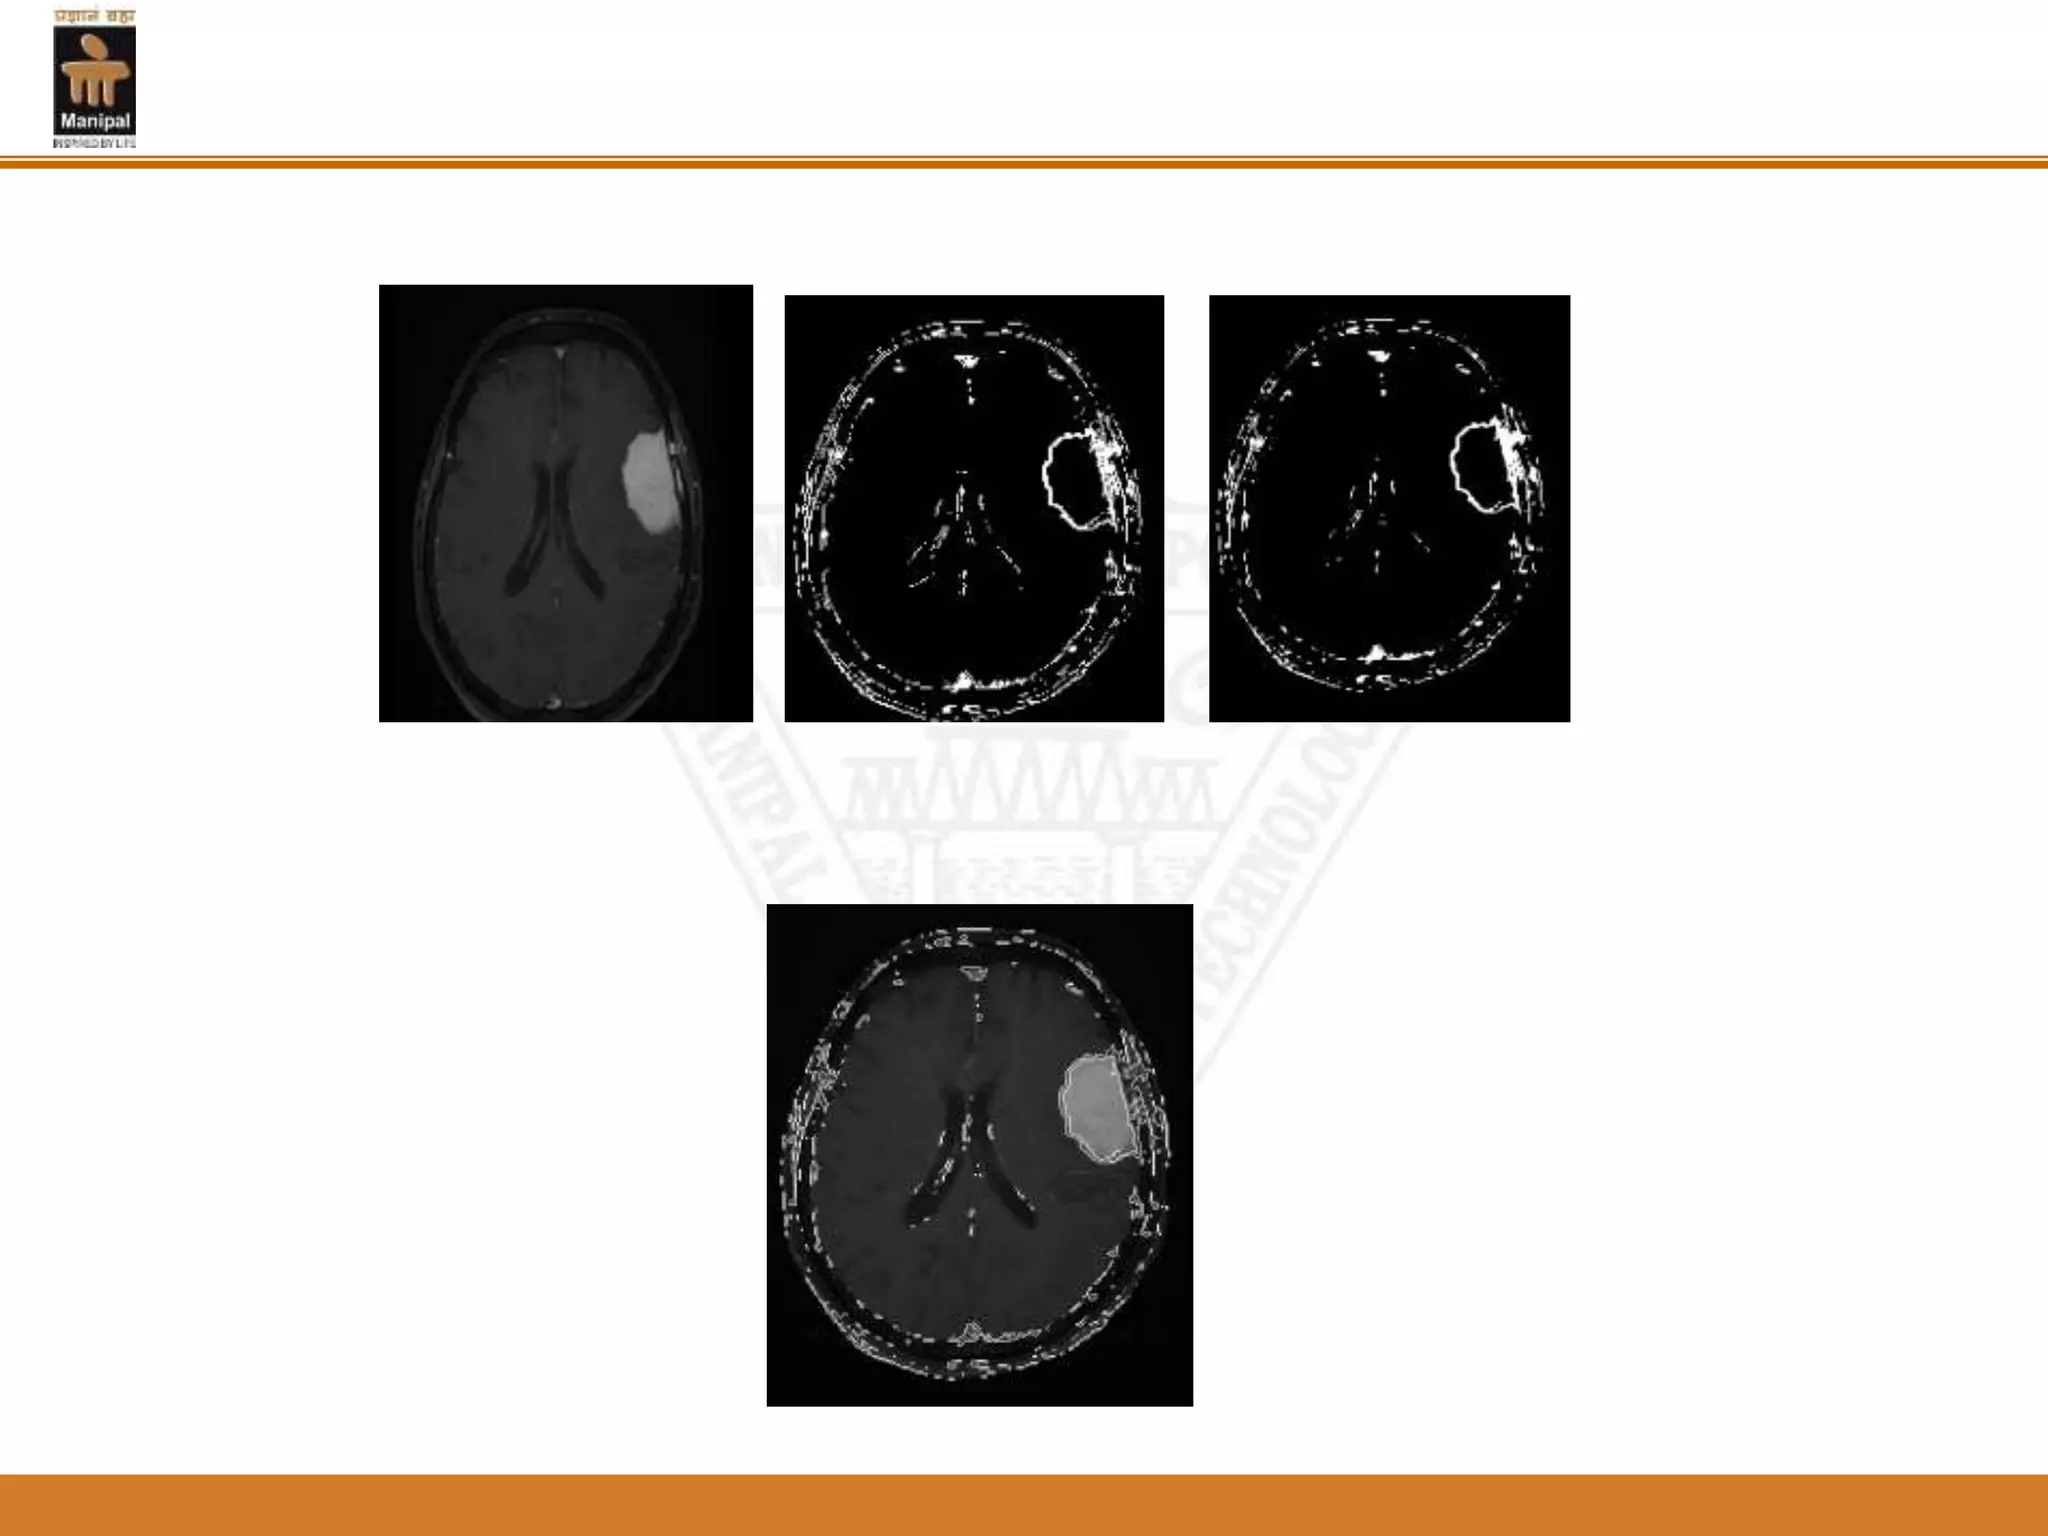

Figure 2: A level set segmentation

Figure 3:The final result

Figure 2: Alevel set segmentation

• 48.